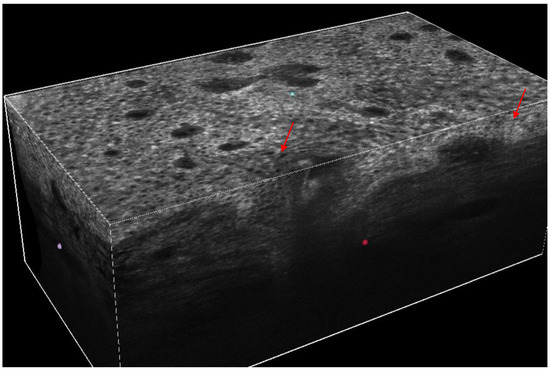

Our present Special Issue will focus on the latest advances in the management of cutaneous malignancies, including the use of various biomarkers, diagnostic devices, imaging techniques (dermoscopy, optical coherence tomography, high-frequency ultrasound, reflectance confocal microscopy, etc.), and novel treatment options. New concepts on early detection, genomic and molecular testing, approaches guiding treatment decisions, and the monitoring of the therapy of cutaneous malignancies are also within the scope. Novel findings on the use of artificial intelligence to enhance the diagnostics of cutaneous malignancies are also welcome. Teledermatology, alone or in combination with artificial intelligence, is also a rapidly developing technology that has a key role in the management of cutaneous malignancies; therefore, it is also included. New data on the background and factors contributing to the development of cutaneous malignancies are of special interest.